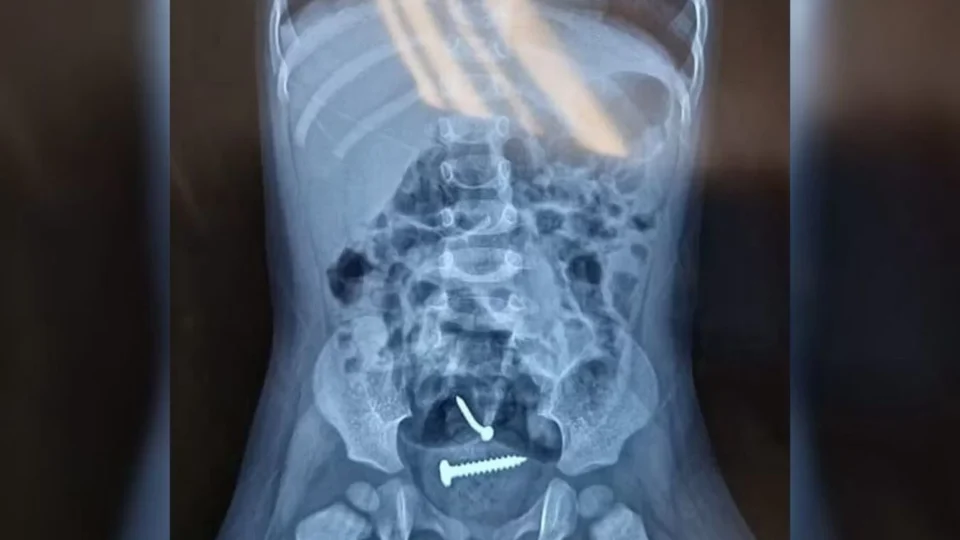

Parafusos no corpo da menina

Elas foram encaminhadas para o hospital e, após a realização dos exames, um raio-X apontou a presença de objetos estranhos dentro do corpo da menina. Ela também tinha lesões nas partes íntimas.

Foto: Divulgação/PM-PI